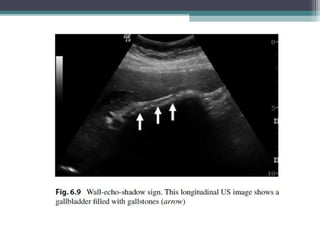

GALL STONES

• USG : Highly sensitive in detecting gall stones and it’s the preferred imaging modality

• Non Impacted stones tend to mobile , echogenic foci in dependent portion with

• posterior acoustic shadowing . (small stones may not shadow ).

• Shadowing can differentiate Gall stones from polyps.

• In order to evaluate Gall stone mobility patient ca be rolled into new position , left lateral

decubitus. Mobile gall stone will roll into the most dependant position. Gall stones adherent to the wall

may not show mobility and don’t show shadowing , can mimic polyp.

• GB filled with Gall stones show DOUBLE ARC SHADOW (Wall Echo Shadow )sign in Gb fossa .

• It consists of Two parallel curved echogenic lines separated by a thin anechoic space with dense

acoustic shadowing distal to the deeper echogenic line.